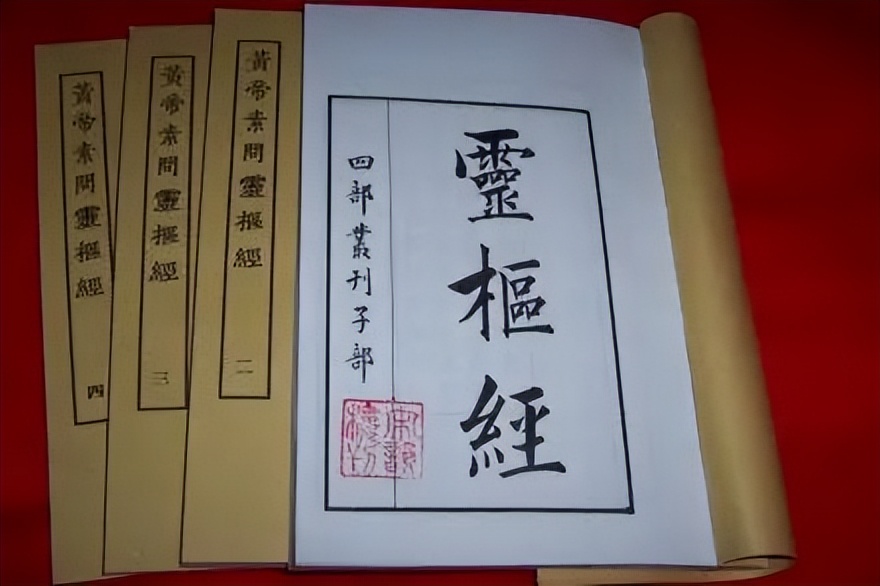

其关于骨伤病分期论治的治疗方法被后世称为“蔺氏七步内治伤损法”,属于《仙授理伤续断秘方》的精髓之一,元代危亦林《世医得效方》提出根据不同分期采用“活血化瘀、养血舒筋、培元补肾”的治疗原则,骨折三期辨证雏形初现。

清代医家将骨折愈合过程概括为“瘀去”“新生”“骨合”3个阶段,与现代医学研究中的骨折生理愈合阶段不谋而合,标志着中医骨伤科三期辨证最终形成,三期辨证体系主张早期治以活血化瘀、行气止痛。

中期治以益气养血、接骨续筋;后期治以培元补肾、强筋壮骨之法。2018版中医骨伤科循证临床实践共识把骨折三期分期定义为早期伤后1~2周、中期伤后3~4周、后期受伤4周后,并推荐采用同证同方进行治疗。

《灵枢·经脉》云:“脉道以通,血气乃行”,脊柱椎体骨折局部椎体骨质骨断筋离、经脉损伤进而血溢脉外、气机逆乱,此使机体呈现出血瘀之征象,症见腰背部刺痛,舌暗红有瘀点,脉弦涩或弦滑;此外加之手术二次创伤,筋脉再次受损导致血溢脉外,气血运行不畅,进而继续加重血瘀之征象。